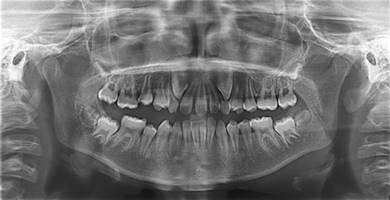

Se realizan estudios complementarios: modelos de estudio, radiografías panorámica y lateral de cráneo, fotos extra e intraorales, para realizar un correcto diagnóstico e el iniciar tratamiento.

La radiografía panorámica (Figura 3) mostró un incisivo único maxilar con una sola raíz y un solo conducto radicular. No se observa formación o impactación del otro incisivo central.